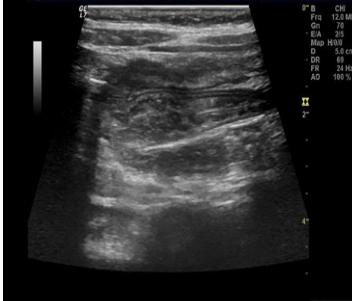

换个角度来看TA的“侧脸”后,在专业人士的眼里中会更加直观。纵断面上侧呈现“假肾征”。这可不是因为“爱疯”换走了孩子的肾,这是心态“膨胀”后的肠管摆出来的独特POSE。

这种看起来像肾脏的“李鬼”在专业人士的眼中自然原形毕露啰